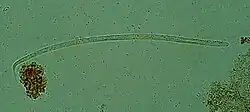

| Onchocerca volvulus, the causative agent of river blindness | |

Onchocerca volvulus is a filarial (arthropod-borne) nematode (roundworm) that causes onchocerciasis (river blindness), and is the second-leading cause of blindness due to infection worldwide after trachoma. It is one of the 20 neglected tropical diseases listed by the World Health Organization, with elimination from certain countries expected by 2025.[2]

Onchocerca volvulus parasites obtain nutrients from the human host by ingesting blood or by diffusion through their cuticle. They may be able to trigger blood-vessel formation because dense vascular networks are often found surrounding the worms.[6] They are distinguished from other human-infecting filarial nematodes by the presence of deep transverse striations.[7]

It is a dioecious species, containing distinct males and females, which form nodules under the skin in humans. Mature female worms permanently reside in these fibrous nodules, while male worms are free to move around the subcutaneous tissue. The males are smaller than females, with male worms measuring 23 mm in length compared to 230–700 mm in females.[7]

The release of oocytes (eggs) in female worms does not depend upon the presence of a male worm, although they may attract male worms using unidentified pheromones.[8] The first larval stage, microfilariae, are 300 μm in length and unsheathed, meaning that when they mature into microfilariae, they exit from the envelope of the egg.[9]